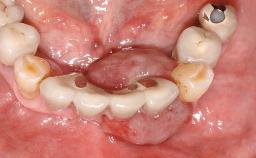

The patient presented with root fracture of the right central incisor with associated distal bone loss. After sectioning and extraction of the fractured root the distal papilla was lost, creating an esthetic compromise. This case demonstrates an option for treating this esthetic compromise. Early (Type 2) implant placement was performed at 7 weeks with simultaneous horizontal and vertical augmentation using Bio-Oss and Bio-Gide (Geistlich). After 3 months a connective tissue graft was performed at the time of implant exposure. Despite these surgical procedures, the papilla could not be recovered. As a result, a prosthetic solution was necessary.